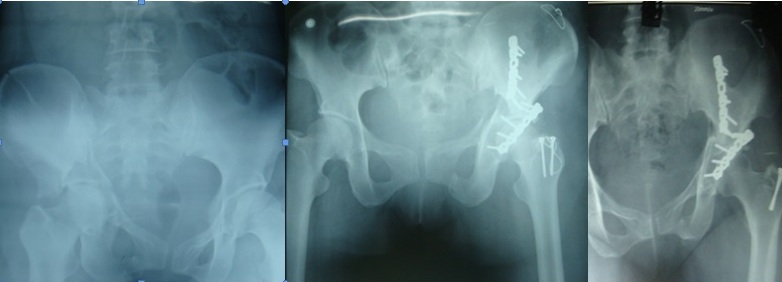

Hình 3: Bệnh nhân Lê Quyết T.: kết quả điều trị

Trong số liệu chúng tôi không gặp các biến chứng như nhiếm trùng, huyết khối tĩnh mạch, các bệnh nhân chỉ có phù nề với mức độ vừa và triệu chứng biến mất dần sau khi vận động trị liệu. Theo dõi các biến chứng muộn, không có khớp giả, đau vùng cùng chậu thắt lưng, chi không ngắn, không có hoại tử chỏm xương đùi cũng như thoái hóa khớp. Trên thế giới số liệu nghiên cứu về vỡ ổ cối đã tăng vọt kể từ 1977, trước năm 1966 có rất ít tài liệu công bố. Các tác giả cho rằng phải theo dõi tối thiểu 1 năm, thời gian trung bình là 5 năm.